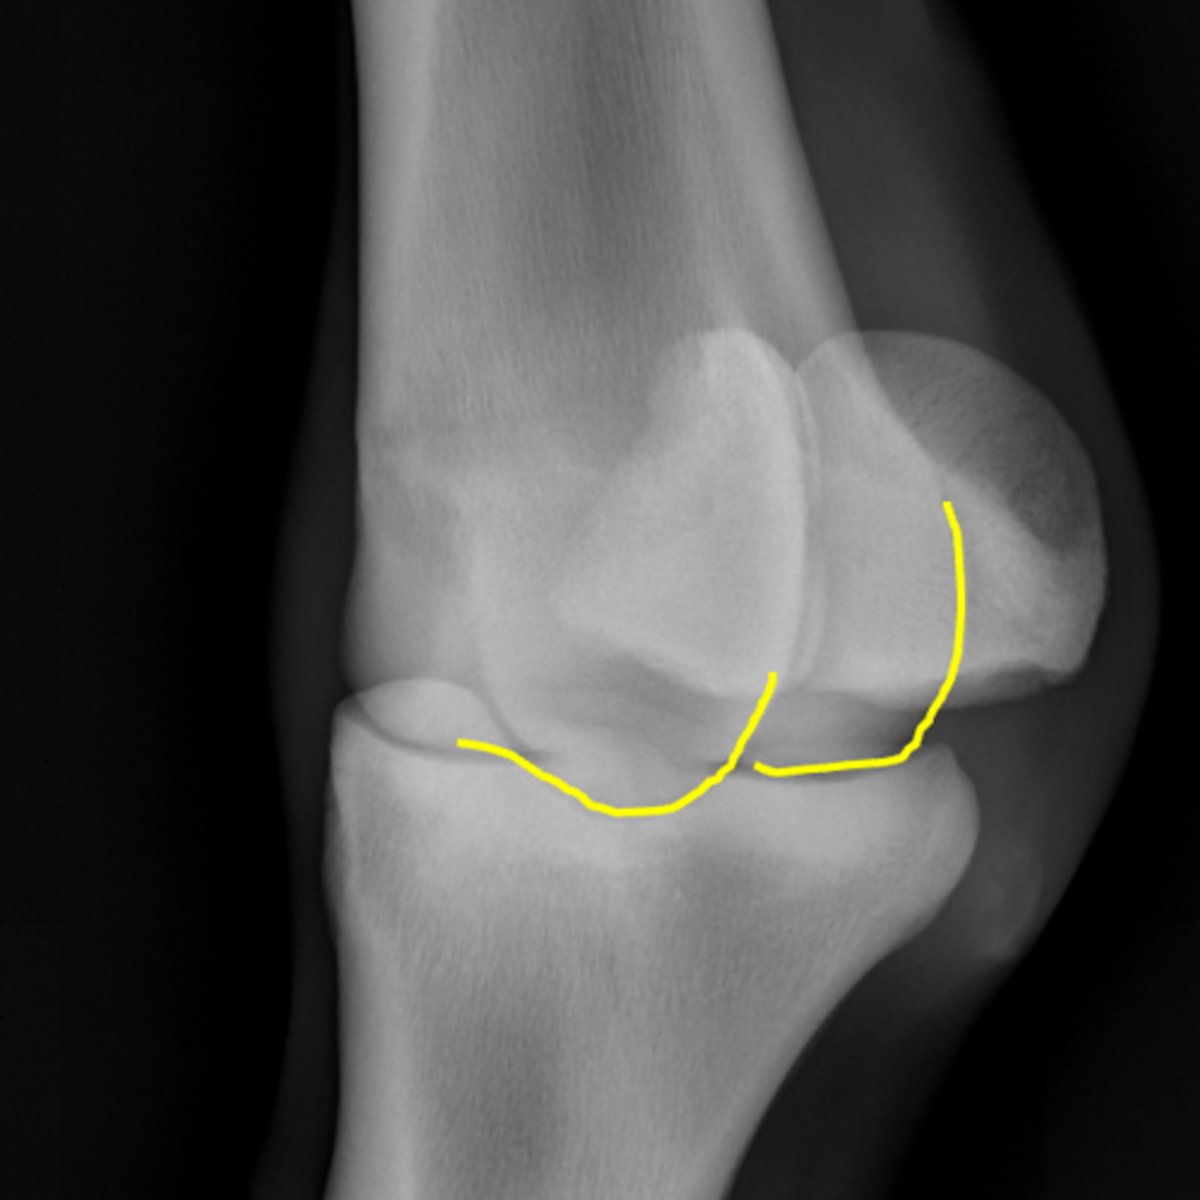

Fetlock joint, flexed LM

ID joint and view

Condyles of the third metacarpal bone